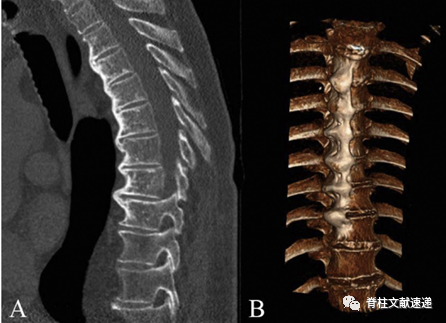

DISH病的特征性病变为椎体间新生骨桥的形成(如下图),从而造成脊柱强直,其导致的后果是脊柱骨折风险升高。强直性脊柱骨折的发生率是非强直性脊柱骨折的4倍,强直性脊柱在受到创伤后没有适当的能量耗散能力,使其更容易发生不稳定、移位骨折。在强直性脊柱中,过伸型(AOSpine-B3)和移位型(AOSpine-C)骨折是最常见的骨折类型,且伴随脊髓损伤的风险高达58%。不幸的是,有19%-41%的DISH病患者发生脊柱损伤后,由于强直性脊柱的形态学变化和骨桥的存在,可能会妨碍创伤性损伤的识别,导致诊断的延误,因此常规 X 光检查可能难以发现损伤,推荐使用CT和MRI来评估 DISH病患者的损伤。

图注:一名70岁男性DISH病患者的CT检查结果,图A为矢状面重建中清楚的显示了超过4个胸椎间新生骨桥的形成。图B为其三维重建的结果。